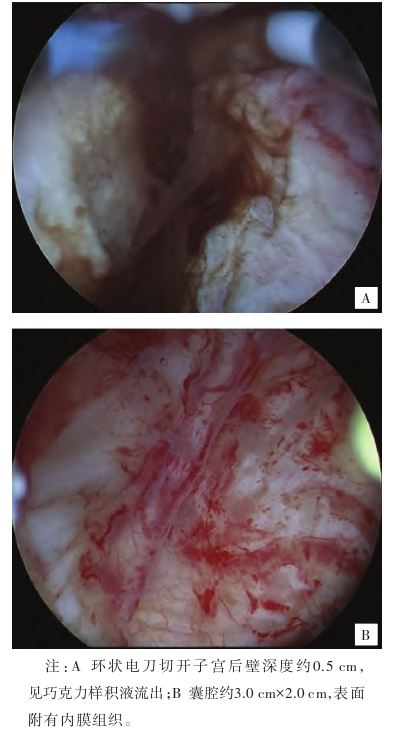

。入院初步诊断:子宫肌壁间子宫内膜异位囊肿。排除手术禁忌证,患者于2024年11月12日在全身麻醉下行宫腔镜

下子宫内膜异位病灶切除术,术中见:子宫内膜薄,色粉红,子宫后壁见一大小约3.0 cm×2.0 cm的肌瘤样凸起,表面光滑,双侧输卵管开口可见,90°环状电刀切开子宫后壁深度约0.5 cm,可见巧克力样积液流出(见图2A),扩大囊腔,膨宫液冲洗干净囊液,见囊腔约3.0 cm×2.0 cm,表面附有内膜组织(见图2B),电切囊腔内膜组织,电切滚珠破坏残余内膜组织,电凝止血,查无活动性出血,退出电切镜。术后病理结果示:可见部分增生期子宫内膜,局部平滑肌增长,其内可见少量子宫内膜腺体排列(见图3)。2024年11月13日患者恢复良好,予以出院。出院诊断:子宫囊性腺肌病。术后分别于2024年11月13日、2024年12月11日、2025年1月8日、2025年2月7日予以注射用醋酸亮丙瑞林微球3.75 mg皮下注射,共4个周期。2024年12月8日于我院妇科门诊复查时自诉腹痛症状完全缓解,CA125(20 U/mL)降至正常,超声检查示:子宫正常大小,后壁肌层查见一大小约17 mm×19 mm中低回声区,边界清,形态规则。2025年2月7日复查超声未见明显异常。2025年4月20日电话随访患者已月经来潮。